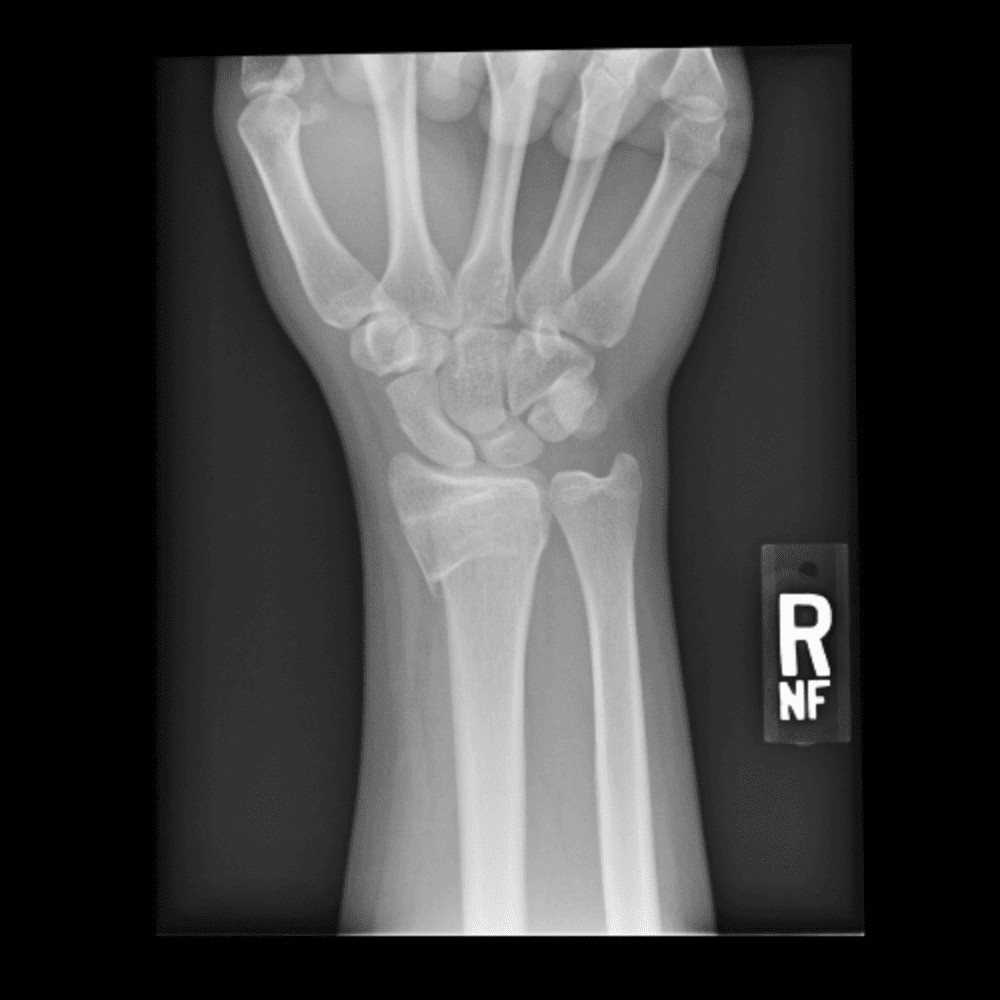

Simulates call by including subtle or difficult cases and some normals.

30 cases